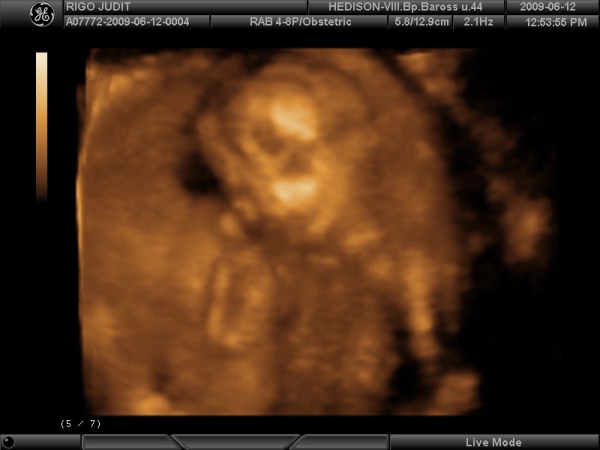

Rólunk csak pár szóban, mert lassan mennem kell:

Megvolt szerdán a 4D uh. Nagyon szép élmény volt. Olyan kis eleven a mi kis babánk, hogy a dokinéni azt mondta, olyan mintha magyar táncot járna. Adott okot a neveteésre is, állítólag rögtön megmutatta, hogy KISLÁNY :) , aztán még többször is volt alkaloom ellenőrizni. Szóval mondta dokinéni, hogy erről a magamutogatásról gyorsan le kell szoktatni. :lol: . Mindene rendben van hála égnek.